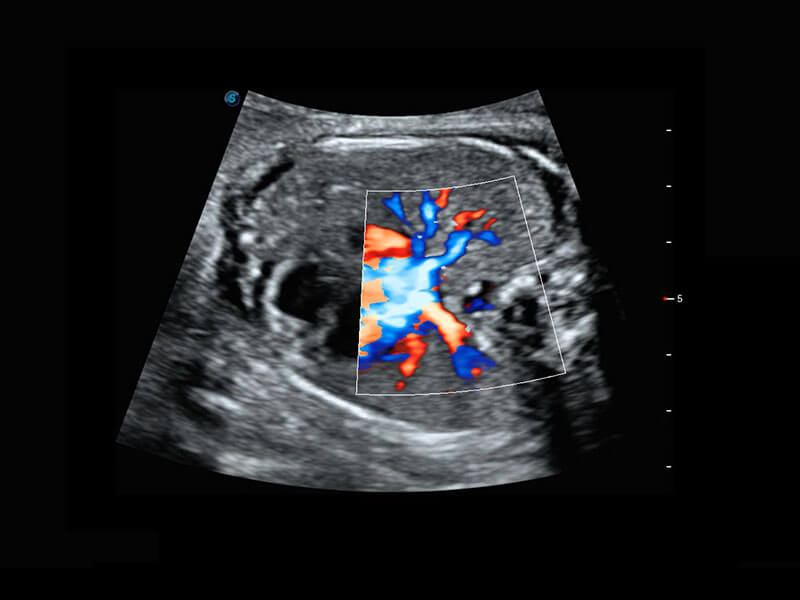

P60优异的图像质量搭载专科探头,在妇科基础疾病的诊断、卵泡生长的监测、输卵管通畅情况的判别等方面为您提供生殖应用方案。

腔内妇科-宫腔分离

腔内妇科-卵巢